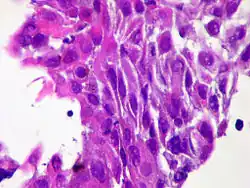

| Micrograph of squamous-cell carcinoma (H&E stain) | |

Squamous epithelial cells are not found in a normal thyroid, so the origin of SCT is not clear. However, it might be derived from embryonic remnants such as thyroglossal ducts or branchial clefts. Often, SCT is diagnosed in one of the thyroid lobes but not in the pyramidal lobe. Another possible way of developing SCT is through the squamous metaplasia of cells. However, that theory is also controversial since Hashimoto's thyroiditis and chronic lymphocytic thyroiditis (neoplasms to be shown squamous metaplasia) are not associated with SCT. Primary STC is usually diagnosed in both lobes of the thyroid gland. The histopathology of STC shows a squamous differentiation of tumor cells.